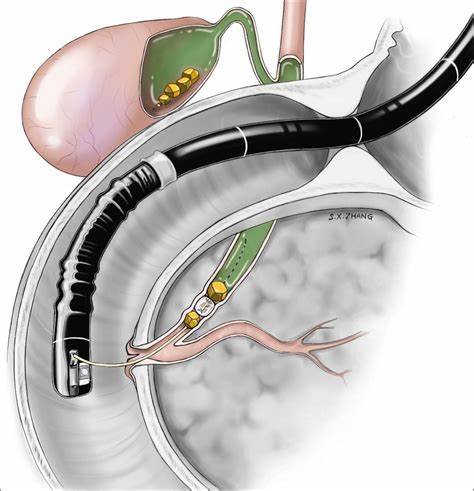

ERCP is a minimally invasive procedure. During this process, a thin flexible tube with a camera is passed through the mouth. It reaches the stomach and small intestine. This allows the doctor to see the bile duct clearly.

In addition, small tools can remove stones or open blocked ducts. Therefore, ERCP treatment in Bhopal helps both in diagnosis and treatment.